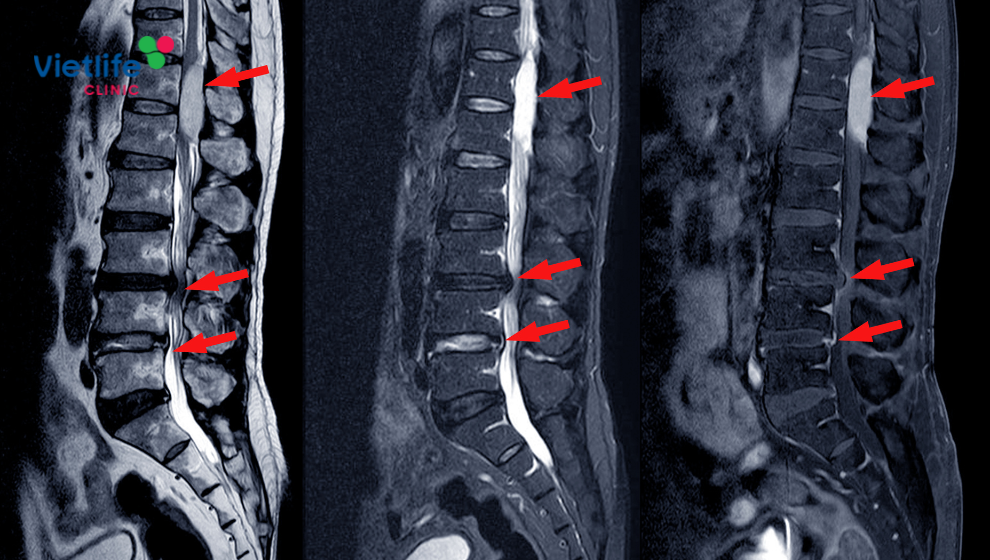

Vùng thắt lưng là nơi chịu nhiều áp lực nhất khi chúng ta đứng, ngồi, mang vác… nên rất dễ bị tổn thương, đặc biệt ở vị trí L4-L5, L5-S1.

- Khám và đánh giá tổn thương bằng MRI hiện đại